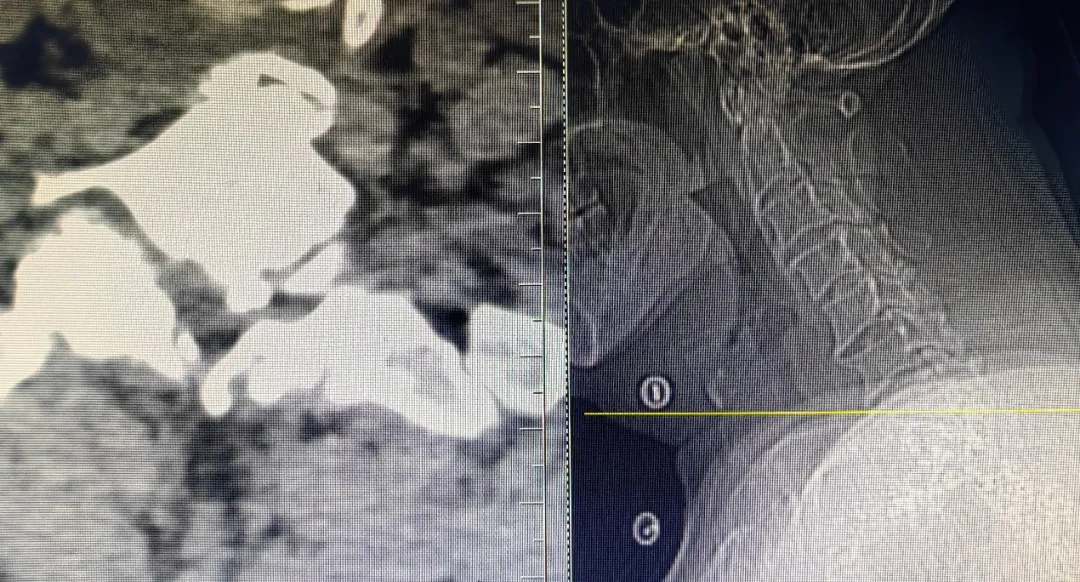

患者,男性,左上肢内侧疼痛剧烈,保守治疗无效,就诊于91直播 脊柱外科中心B区,诊断为神经根型颈椎病,C7/T1节段,左侧神经根管骨质增生严重,颈前路手术因胸骨阻挡难以实施,后路手术减压风险高、担心减压不彻底且创伤大。赵文奎博士了解患者病情后,用北医三院的诊疗理念,从影像学资料研判、诊断与鉴别诊断、治疗方案的制定等不同方面进行了详细分析,与91直播 脊柱外科中心B区医疗团队共同为患者制定了“精准化”手术方案——经皮内镜颈椎椎板切除神经根管减压术。

上图为术后复查CT

可见神经根管较术前变宽